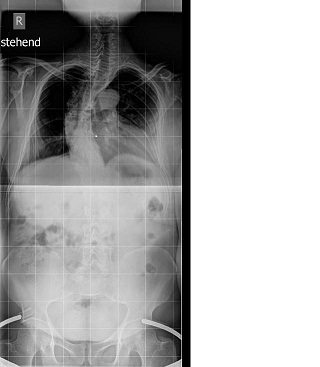

Das sind nun meine Aufnahmen vom 22. Februar 2010

Hallo liebe Foris !Bodo hat geschrieben:Das sind nun meine Aufnahmen vom 22. Februar 2010

Ich habe die relativ schlechten Aufnahmen durch bessere ersetzt .

- Aufnahme zwei Tage vor der Relaese OP

- Röbi Aufnahme vom 7.11.2010 in Neustadt vorne.JPG (25.39 KiB) 8829 mal betrachtet

- Röbi Aufnahme vom 7.11.2010 in Neustadt.JPG (26.91 KiB) 8829 mal betrachtet

- Aufnahme nach der Versteifungs OP

- Röbi Aufnahme vom 6.12.2010 in Neustadt.JPG (8.95 KiB) 8829 mal betrachtet

- Aufnahme nach der Versteifungs OP von vorn

- Röbi nach der Versteifungs OP vom 6.12.2010 in Neustadt.vorne.JPG (21.26 KiB) 8829 mal betrachtet